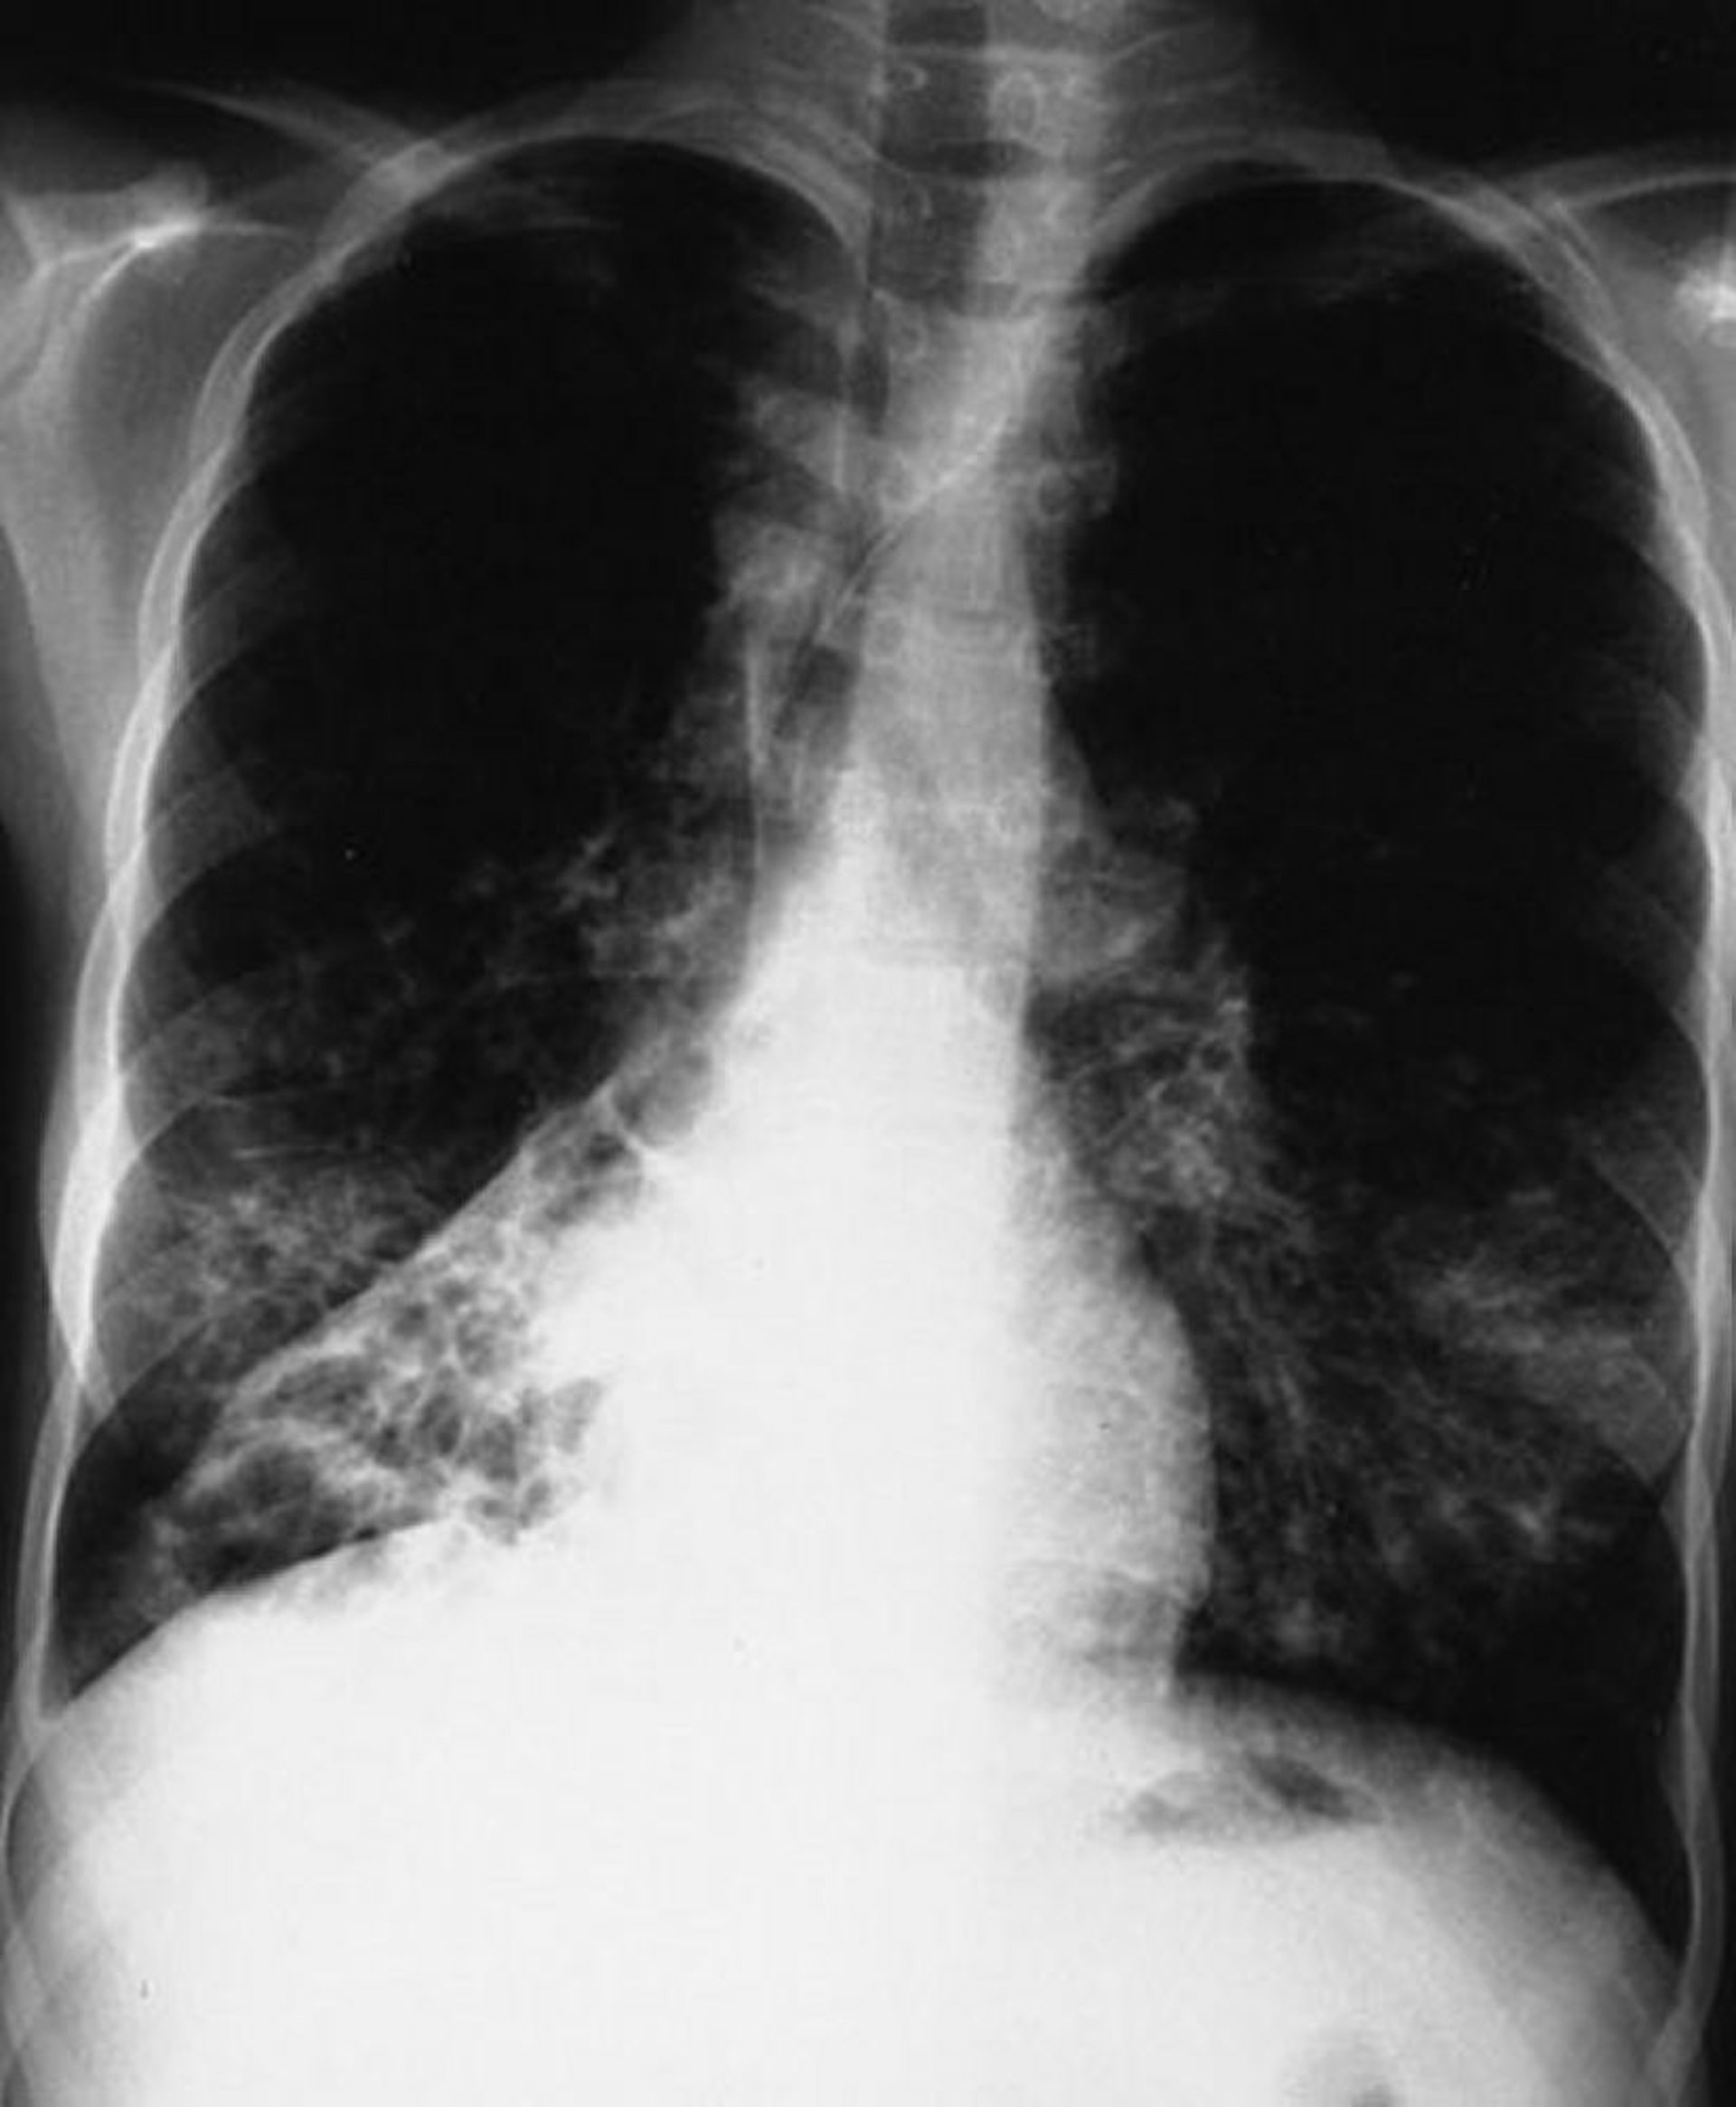

Mucoviscidose (fibrose kystique) (radiographie de thorax)

Cette radiographie pulmonaire montre un effondrement du lobe inférieur droit. Les signes sont typiques de la mucoviscidose mais ne sont pas spécifiques.